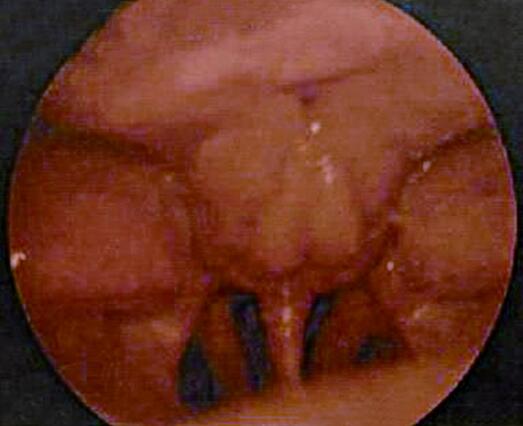

程××,52岁,男,主诉发现右颈下颌角前下方无痛性肿块1个月,回缩涕中带血半年,于门诊就诊。体检示:病人神志清、应答切题,食欲正常,两便正常。体重无明显减轻。右颈下颌角前下方有一直径2c m 肿块,质地偏硬,不活动,无压痛。间接鼻咽镜检查见:鼻咽部顶后壁黏膜粗糙不平,肉芽组织状肿物(图5‐2)。为进一步明确诊断,医师拟定进一步检查:纤维鼻咽镜检查、CT 及MRI 检查和鼻咽部新生物活检。

图5‐2 鼻咽顶后壁新生物